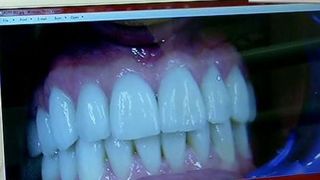

Medicul Coffi Dima a facut o serie de marturisiri halucinante in cazul lui Cristian Boureanu. Specialistul in implantologie si estetica dentara sustine ca dantura fostului parlamentar este distrusa intr-o proportie mare.

Ba mai mult decat atat, medicul a ramas uimit cand a vazut imaginile trimise de Laura, iubita lui Boureanu, imediat dupa pumnul incasat si este de parere ca un pumn nu are cum sa distruga atatia dinti. Coffi Dima mai spun ca este posibil sa se fi lovit cu gura de asfalt in momentul in care a ajuns.

Am crezut ca este vorba de cateva fisuri si ca voi termina repede, insa cand am vazut despre ce este vorba, cat de grav, mi-am dat seama ca nu pot sa-l rezolv pe loc. Are dureri, este normal sa aiba dureri. Asta a fost si rugamintea Laurei, sa-l programez cat mai repede pentru ca are dureri groaznice. Dintii au nervi si are mai multi dinti afectati. Unul dinte ei este pur si simplu retezat.

Incisivul lipseste de la nivelul gingiei. Fatetele lipsesc. Mi-a fost greu sa-l vad asa, banuiesc ca pentru el a fost si mai greu", a declarat medicul lui Cristian Boureanu pentru WOWbiz.